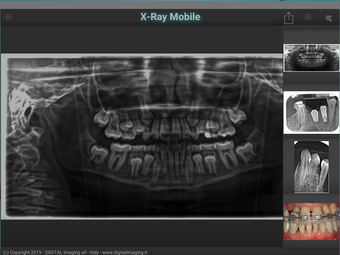

X-Ray Mobile: Acquire X-Ray Images on Your Android Device

X-Ray Mobile is an Android app that allows users to acquire x-ray images directly on their mobile device. This app is especially useful for those in the medical field who need to take x-rays on the go. With X-Ray Mobile, users can also capture pictures from their camera and send them to a connected PC. The app uses WiFi to connect to the PC, making it easy to transfer images quickly and efficiently.

The interface of X-Ray Mobile is simple and easy to navigate. Users can easily switch between the camera and x-ray modes, making it easy to capture the images they need. The app also includes a number of settings that allow users to adjust the brightness and contrast of their images. Overall, X-Ray Mobile is a useful tool for anyone who needs to take x-rays on the go.